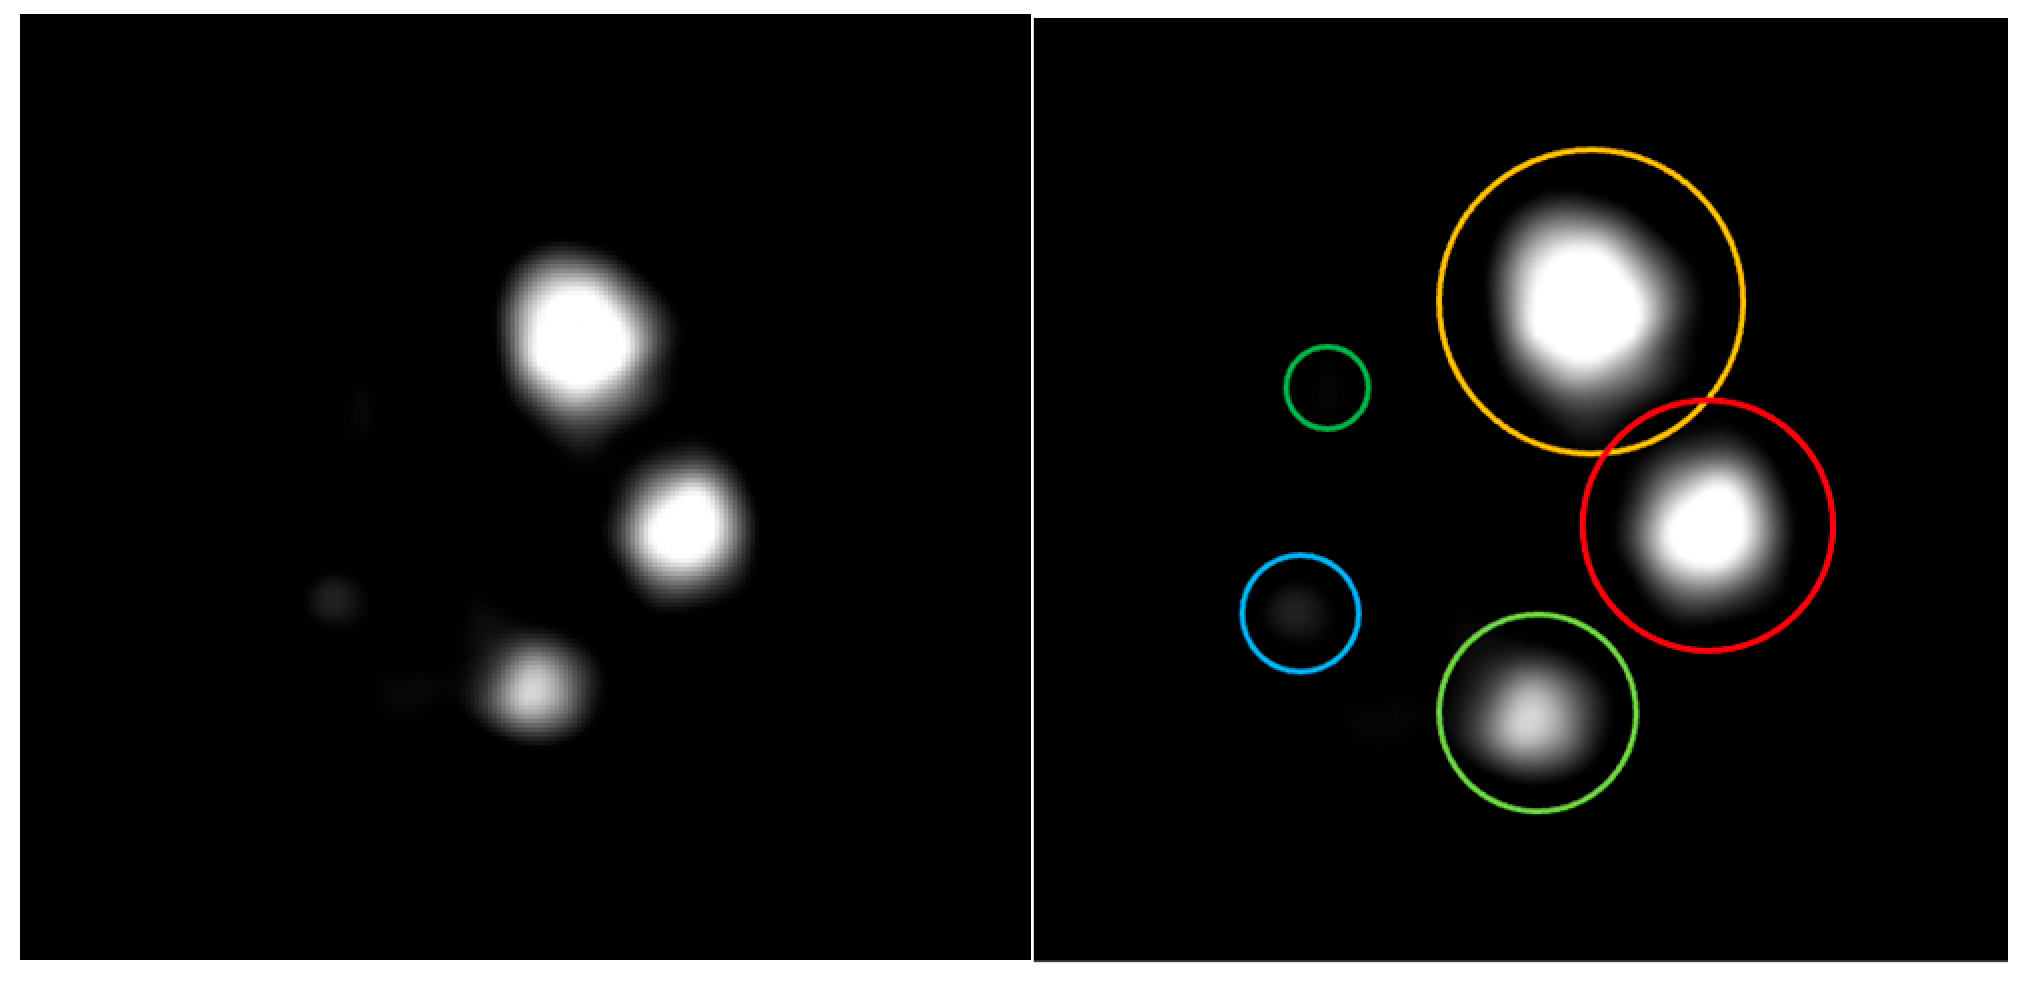

3.3. Micro Derenzo Phantom